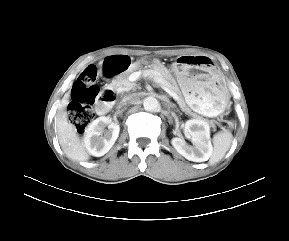

标题: CT19533:病变来源于哪?

患者,男,发现上腹部包块两月余。

病变位于肝胃间隙,实际就是位于小网膜囊(左肝下后间隙),呈轻度不均匀性强化,腹腔内及腹膜后见多发肿大淋巴结。所以我考虑肝胃间隙恶性胃肠间质瘤并淋巴结转移。

病灶强化不显著,灶周及腹膜后见多量淋巴结肿大,考虑淋巴瘤可能,其次考虑间质瘤

病灶与胰腺分界不清,来源于胰腺?

强化后病变与胃壁分界清楚,并且血供不是来源胃壁血管。考虑胰腺颈体癌并腹腔腹膜后淋巴结转移。

肝胃韧带内及腹膜后可见多发增大的淋巴结影,首先考虑转移.